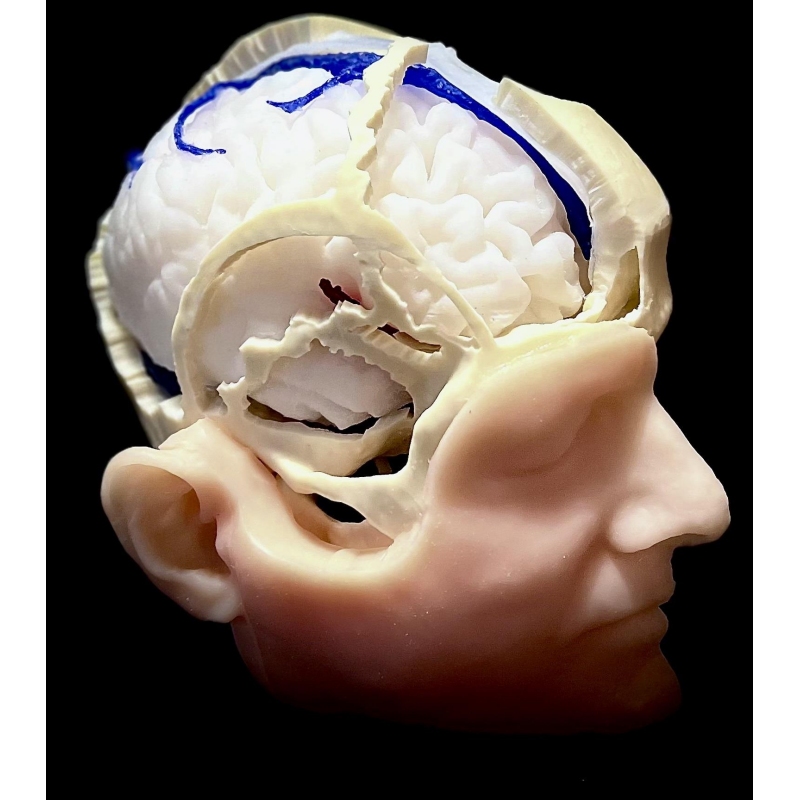

Človeška lobanja z vsemi kraniometričnimi točkami, razpokami in kanali. 1:1, pomanjšano na podlagi resničnega človeškega CT-posnetka na podlagi s podobnimi lastnostmi vrtanja kot človeška kost. Vključuje kožo, intrakranialno možgansko ovojnico, falx, tentorium, venske sinuse in vse lobanjske živce, arterije ter možgane, možganovino in možgansko deblo. Patologija: meningiom olfaktornega žleba, meningiom sfenoidnega krila, parafalcinalni meningiom, trigeminalni švanom in vestibularni švanom. Vse je bilo pridobljeno iz resničnih primerov, vključno s slikami DICOM za predoperativno načrtovanje.